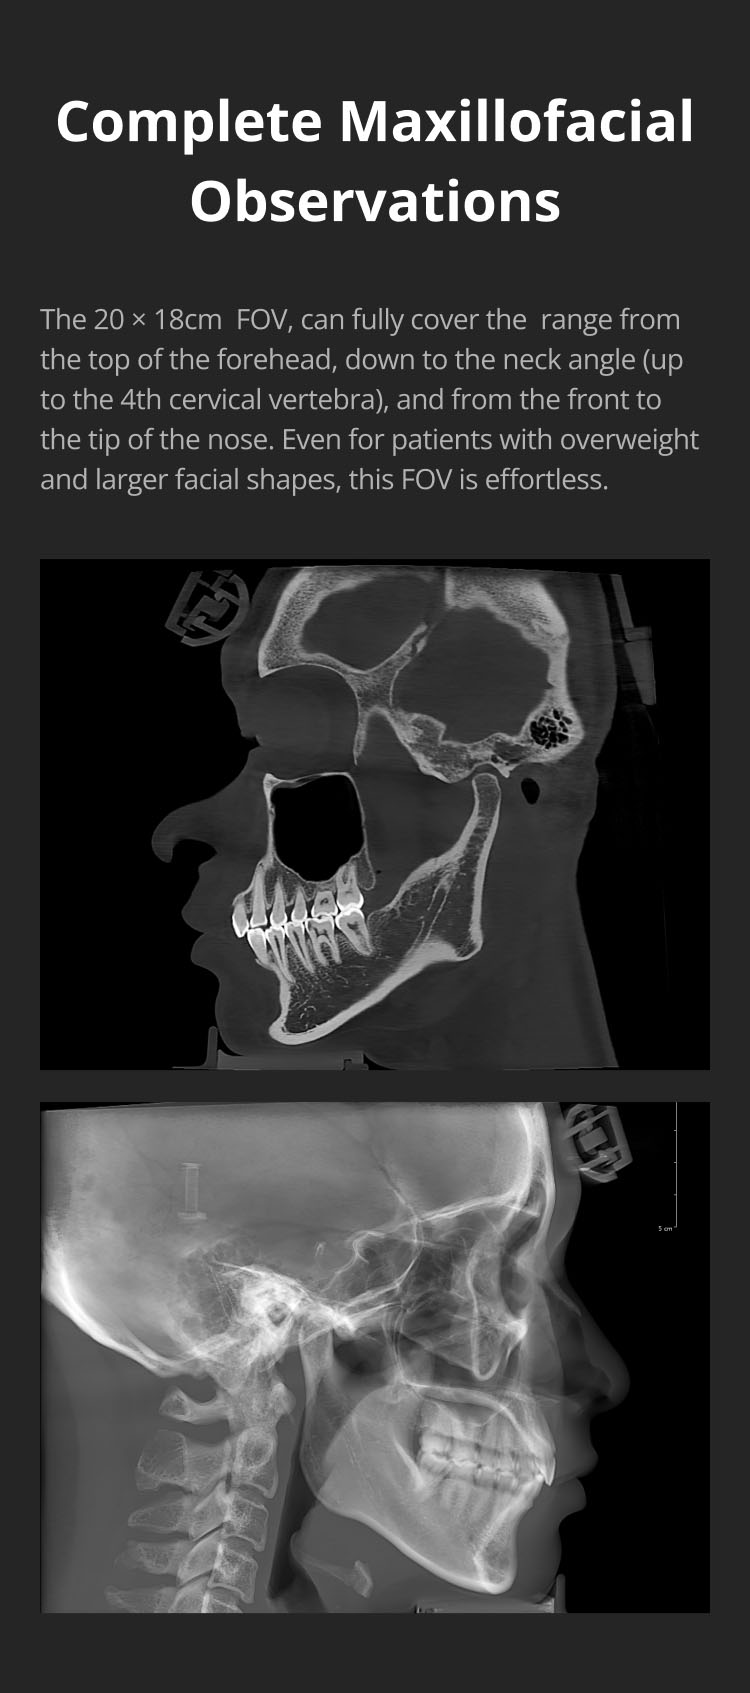

The 20 × 18cm FOV, can fully cover the range from the top of the forehead, down to the neck angle (up to the 4th cervical vertebra), and from the front to the tip of the nose. Even for patients with overweight and larger facial shapes, this FOV is effortless.